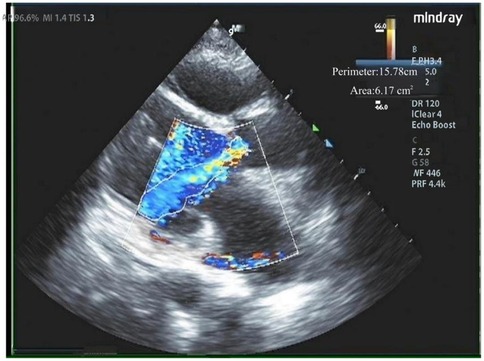

Preoperative CT evaluation

The patient had a regurgitant tri-leaflet aortic valve with a normally shaped, elliptical-like annulus. The valve leaflets showed no thickening, calcification, or commissural fusion. The annular circumference measured 62.3 mm, with a circumference-derived diameter of 19.8 mm. The diameter of the left ventricular outflow tract (LVOT) exceeded that of the annulus during diastole, giving it an overall funnel-like appearance. The supra-annular region was nearly cylindrical, posing significant challenges for anchoring and elevating the risk of valve migration. Specific measurement data can be found in Figure 2. According to current guidelines, in patients with AR, larger self-expanding valves are generally preferred compared with those used for aortic stenosis, in order to achieve stronger radial force and anchoring. The guidelines recommend an oversizing ratio of prosthetic valve diameter relative to the annular diameter of 15%–30%. The valve selection in this case followed these principles. Based on the preoperative CT evaluation and the absence of significant calcification of the native aortic valve, a Taurus Trio 25 valve (size: 28 mm) was ultimately implanted via the right femoral artery approach to achieve optimal radial support and anchoring stability. The Taurus Trio TAVR system is designed on the basis of the JenaValve Trilogy transcatheter heart valve technology (4). Its unique locator elements enable secure anchoring even in the absence of calcification, effectively preventing valve migration toward the LVOT while ensuring precise coaptation with the native leaflets. This design promotes long-term hemodynamic stability and preserves the possibility of future percutaneous coronary interventions (PCI).

Figure 2

Preoperative CT evaluation. (A) Annular circumference diameter: 19.8 mm; (B) outflow tract circumference diameter: 23.2 mm; (C) sinus of valsalva circumference diameter: 31.3 mm; (D) sinus of valsalva diameter: 31.8 mm, 29.5 mm, 31.9 mm; (E) sinutubular junction circumference diameter: 27.5 mm; (F) aortic circumference diameter 4 cm above the annulus: 34.3 mm; (G,H) no significant calcification observed in the annulus and leaflets; (I) height of the left coronary artery ostium: 11.9 mm; (J) height of the right coronary artery ostium: 9.3 mm.